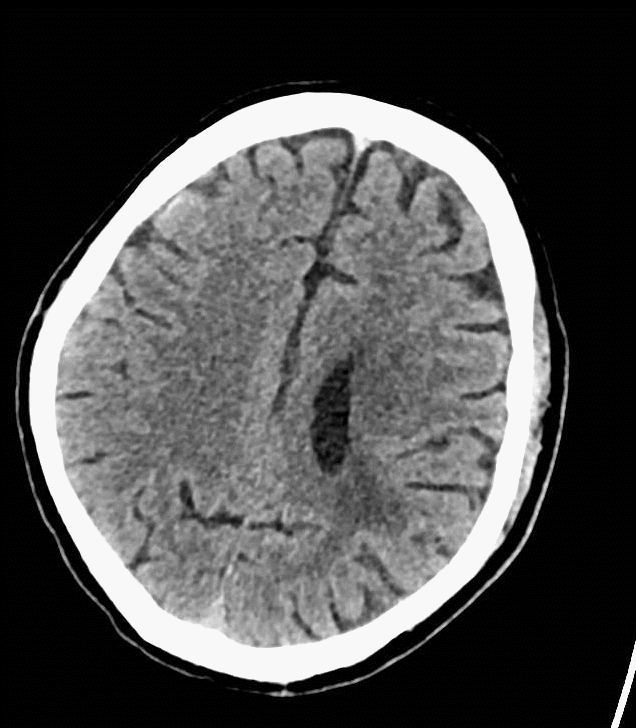

术后复查:颅脑CT平扫未见明显新增脑梗塞。

复查颅脑CTA及CTP,改善明显。